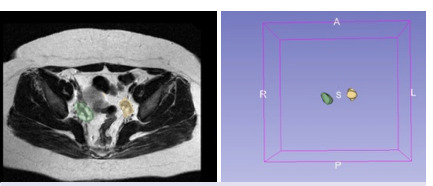

Methods: The study included patients diagnosed with PCOS who had undergone pelvic MRI in the endocrine department between 2014 and 2022, along with an age-matched control group. The ovaries were manually segmented from T2-weighted images using the 3D Slicer software. Both first- and second-order features, including wavelet filters, were extracted from the images. Utilizing the Python 2.3 programming language and the Pycaret library, various machine learning algorithms were employed to identify highly correlated features. The optimal model was selected from the 15 algorithms assessed.